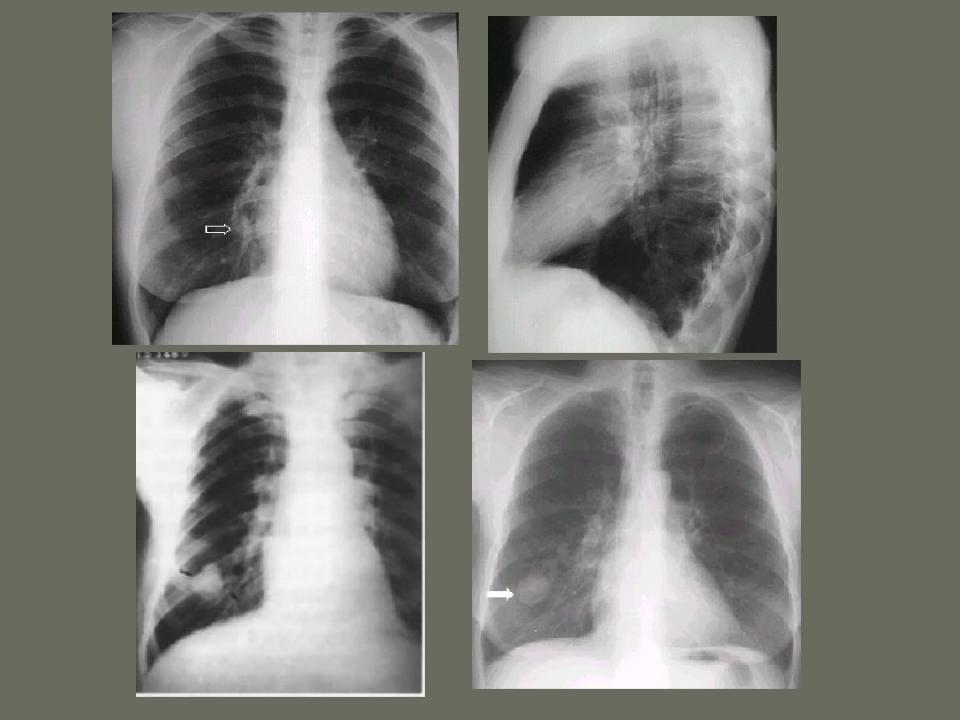

肺部先天性疾病的影像诊断